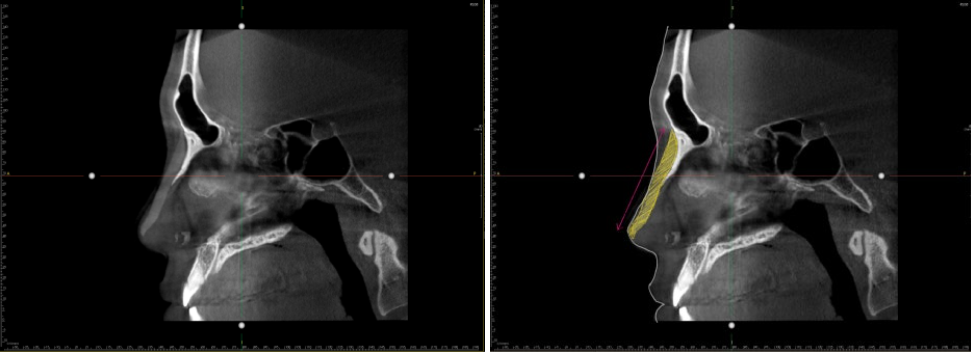

The CT scan image confirmed that the silicone implant was inserted until the nose tip. The area highlighted in yellow is the silicone implant.

Based on the CT scan results, a detailed surgical plan was developed as follows:

a) Removal of existing silicone implant: Safely removing the silicone implant inserted all the way to the tip of the nose that presented a risk.